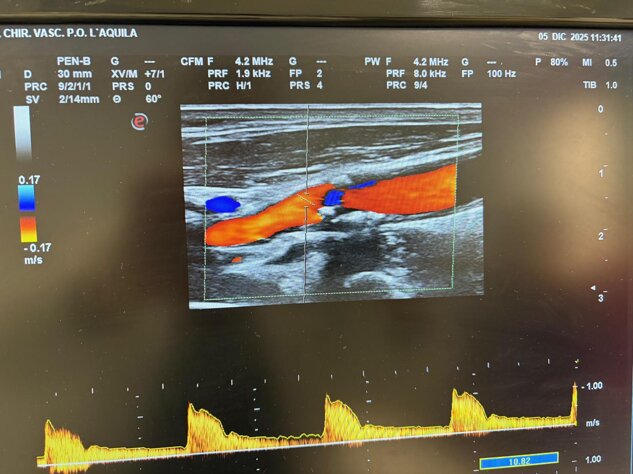

Controllo ecocolordoppler EVLT vena grande safena

Obliterazione VGS di coscia